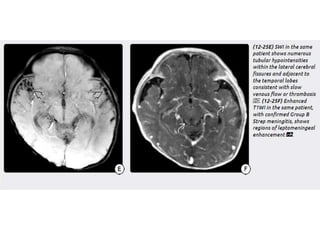

Cerebral Malaria

• Cerebral malaria (CM) is caused by infection with the protozoan

parasite Plasmodium and is transmitted by infected Anopheles

mosquitoes. P. falciparum has the most severe morbidity and

mortality and causes 95% of all CM cases.

• Cerebral malaria is a rare intracranial complication of a malarial

infection.

• Cerebral malaria should be suspected when there are neurological

symptoms on a background of malarial infection.

• Clinical presentations include: headache, altered state of

consciousness, seizures, backache, vomiting, nausea, etc.

Imaging

Imaging findings on NECT vary from normal to striking.

• The most typical finding is focal infarcts in the cortex, basal

ganglia, and thalami.

• Gross hemorrhage can occur but is rare.

• Diffuse cerebral edema can occur in severe CM.